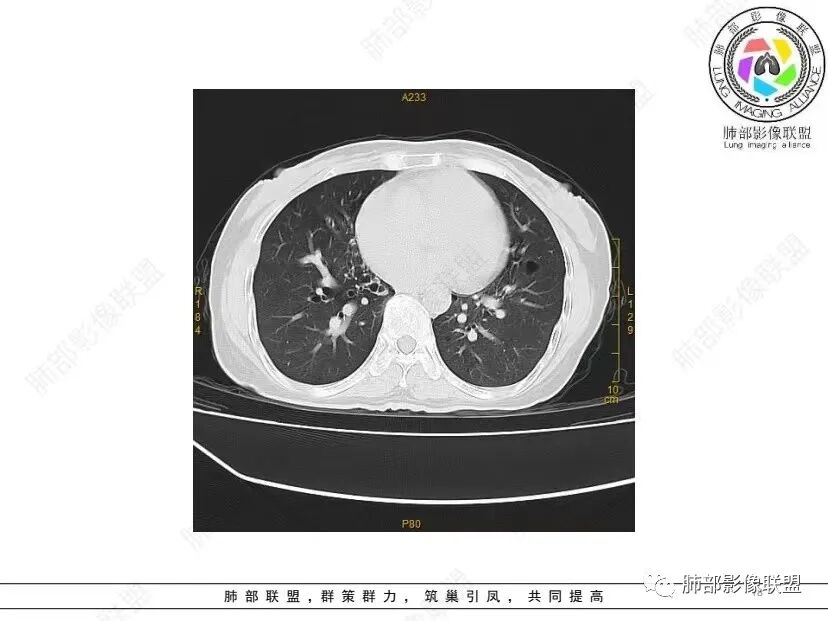

秦化君: 晨读 双肺不均匀散在多发囊状影,大小不等,部分囊形态欠规整,壁薄均匀,部分囊胸膜下平行。双肺少许斑片状磨玻璃影,边缘模糊。考虑BHD综合征。鉴别PCP,LIP。

红日初升: 中年女性,双肺多发气囊,背景干净,大小不一,下肺韧带旁较大,考虑BHD,鉴别LIP、LAM

宇宙: 中年女性,两肺多发大小不等薄壁囊状影,两肺纵膈胸膜下分布明显,考虑BHD,鉴别LAM

这个病例目前影像特点,多囊,囊主要位于下肺,胸膜下及小叶核心为主

伴随少许索条,而且这些病灶与囊不一定有相关性

囊的分布,PLCH基本可以排除

囊壁薄且均匀,光滑,形态规则,基本除外恶性

单纯囊,无斑片及其他实性病灶,感染不支持,可能的是:LAM、BHD、LIP

从囊的分布、大小,BHD可能性可能大一些,但是LIP、LAM都可以这样表现,具体诊断应该是这三种之一,影像缩小到这里我觉得就差不多了,结合临床考虑就行,不支持靠影像强下结论。

临床诊断BHD综合征需要满足一个主要或两个次要标准。主要标准包括:1、皮肤上至少发现5个纤维滤泡瘤,至少1个组织学证实;2、致病的FLCN种系突变阳性。次要标准:1、多发肺囊肿,双侧基底部,有或无自发性气胸;2、肾癌,起病早(<50岁)或多灶性或双侧;3、 BHD综合征一级亲属。BHD主要影像表现特征:1、两肺内肺囊肿:80%以上的BHD患者会出现肺内囊肿,且倾向于基底部近胸膜下分布,特别是纵隔侧肺膜下,囊肿形状不规则、囊肿可大可小,肺内囊肿多毗邻肺下动脉或静脉近端,胸部CT上囊肿分布和特点对诊断有提示意义。2、继发自发性气胸:BHD患者发生气胸风险是正常人的5倍,BHD患者的气胸发生率约为1/4,气胸复发率则高达59%。3、肾肿瘤:(常为双侧性、倾向于嫌色细胞组织学亚型)4、皮肤表现:(为面、颈部纤维性毛囊瘤、毛盘瘤)